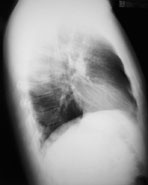

Ein 41-jähriger Mann sucht Sie auf, weil er zum dritten Mal in diesem Winter erkältet ist und dieses Mal sogar mit Fieber. Er gibt ausserdem an, etwas trockenen Husten zu haben. Ausserdem besteht seit Wochen eine Sinusitis, die nicht so recht abheilen will.

Gewichtsverlust wird verneint. Der Patient ist Nichtraucher und fühlte sich bis anhin gesund.

Die Lungenperkussion und -auskultation ist unauffällig. Das Labor zeigt eine Leukozytose ohne Linksverschiebung und ein CRP von 97 mg/dl. Hier das Röntgenbild der Lunge:

Thorax pa

Thorax seitlich

Welche Befunde fallen Ihnen auf?

Es ist klar, dass aufgrund dieses Befundes keine Diagnose gestellt werden kann. Welche Diagnose ist aufgrund der Klink und des radiologischen Befundes am wahrscheinlichsten?